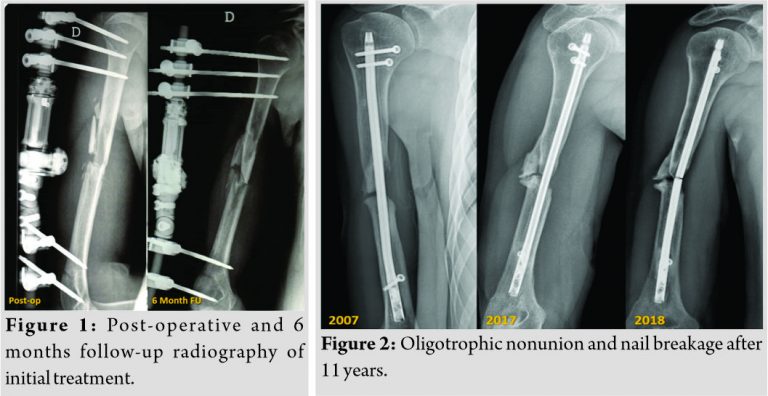

A 33-year-old man referred to our hospital with oligotrophic nonunion of the middle humeral diaphysis and nail breakage. He had a history of Gustilo type I open fracture 12 years before (May 2006), secondary to a motorcycle accident, with a multifragmentary pattern (Arbeitsgemeinschaft für Osteosynthesefragen/Orthopedic Trauma Association type 12B3). He had been initially treated with debridement, wound closure, and positioning of a uniplanar external fixator. After 6 months of clinical and radiological follow-up, there were no signs of healing and persistent pain at fracture site (Fig. 1). It was then decided to convert the external fixator into a roamed retrograde IM nail. The patient was followed up clinically and radiologically until 2017 and had returned to his normal life without complaining of any pain during everyday life and working activity. Unfortunately, unlike the good clinical outcome, the follow-up X-rays showed an oligotrophic nonunion of the midshaft of the humerus with, at least, 1 cm of bone loss. A year later(May 2018), the patient came to our attention because, after a mere twisting movement, he heard a snap and, subsequently, pain and loss of function to the right arm. With plain radiographs, a nail breakage was assessed (Fig. 2). He complained of moderate pain and functional disability of the involved limb and was then admitted to our hospital. Full blood count, sedimentation rate, and C-reactive protein level were preoperatively investigated for infection and were negative. We decided then to schedule a one-stage surgical procedure of nail removal and new osteosynthesis with autogenous iliac crest bone graft. After regional nerve block and general anesthesia, the patient is seated in a lazy beach chair position, with the head of the bed elevated approximately 30°. This position allows good surgical exposure of the humerus and eases access to the iliac crest. In addition, a padded bump is placed under the ipsilateral hip to ease in the access of the iliac crest by increasing the crests’ prominence. The humeral nonunion was exposed through an extended anterolateral approach. A straight incision at the lateral border of the biceps muscle was made, and, after cutting the fascia, the biceps muscle was retracted medially, bringing the brachialis muscle into view. The brachialis muscle was split longitudinally throughout its lateral third and transected down to the bone. Through deltopectoral surgical exposure, the two proximal screws were removed. Distally, the radial nerve was identified, surrounded with a vessel loop and the distal screw was then removed. The nonunion zone was debrided by removing all fibrous tissue, interposed muscle, and necrotic bone followed by decortication, until bleeding bone was observed to provide a viable bed for the bone graft and to stimulate callus formation. The debridement left almost 2 cm bone gap and exposed the broken nail which was removed. A tricortical bone graft is obtained from the iliac crest according to previously described technique [16]. The iliac crest graft was trimmed to enable it to snugly telescope into the fracture fragments (the harvested bone graft was then packed into the defect) and then, a 4.5mm limited contact dynamic compression plate was placed on the anterior face of the humerus (Fig. 3). Dynamic examination of the synthesis under fluoroscopy has been used as an intraoperative method to assess the stability of the construct. Wound closure was provided. Three sets of intraoperative cultures were done with negative results. Post-operative X-rays showed good alignment of the nonunion and refilling of the bone defect. The patient was allowed early rehabilitation with free shoulder and elbow motion to avoid joint stiffness. He was followed up radiologically at regular time intervals of 4 weeks and clinically with Constant shoulder score (CS), subjective shoulder value (SSV), and visual analog scale (VAS). Visits were scheduled until bone graft union was radiologically confirmed at final follow-up (Fig. 4). At this point, good clinical function was achieved with SSV of 80%, VAS 0, and CS of 76 (Fig. 5).